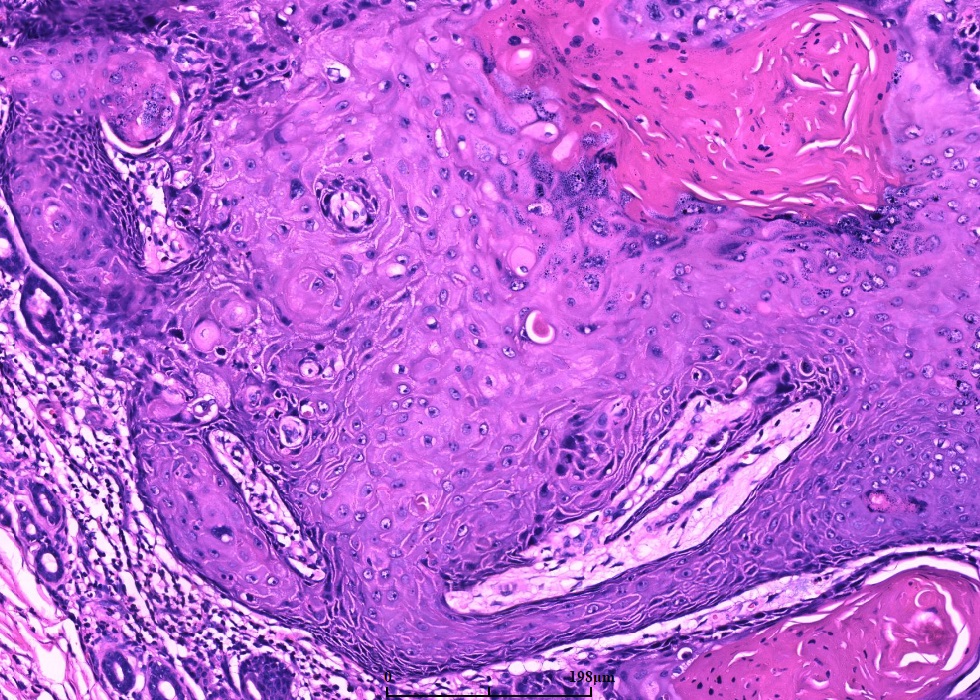

早期呈界限清楚的由大的鳞状上皮构成的实性叶状结构,角化少,细胞异型轻微;

随着病变进展,中央出现火山样结构,内含角化细胞及角化物,无颗粒细胞;

鳞状上皮巢不规则向深部浸润,但轮廓光滑,一般不会超过附属器的水平,深部的上皮细胞巢或上皮脚顶端可出现角化珠和上皮内中性粒细胞微脓肿;

角质形成细胞胞质丰富、强嗜酸性,细胞异型程度不等,但通常较轻且局限于基底细胞层;

周围常伴有炎症反应,但无浆细胞;